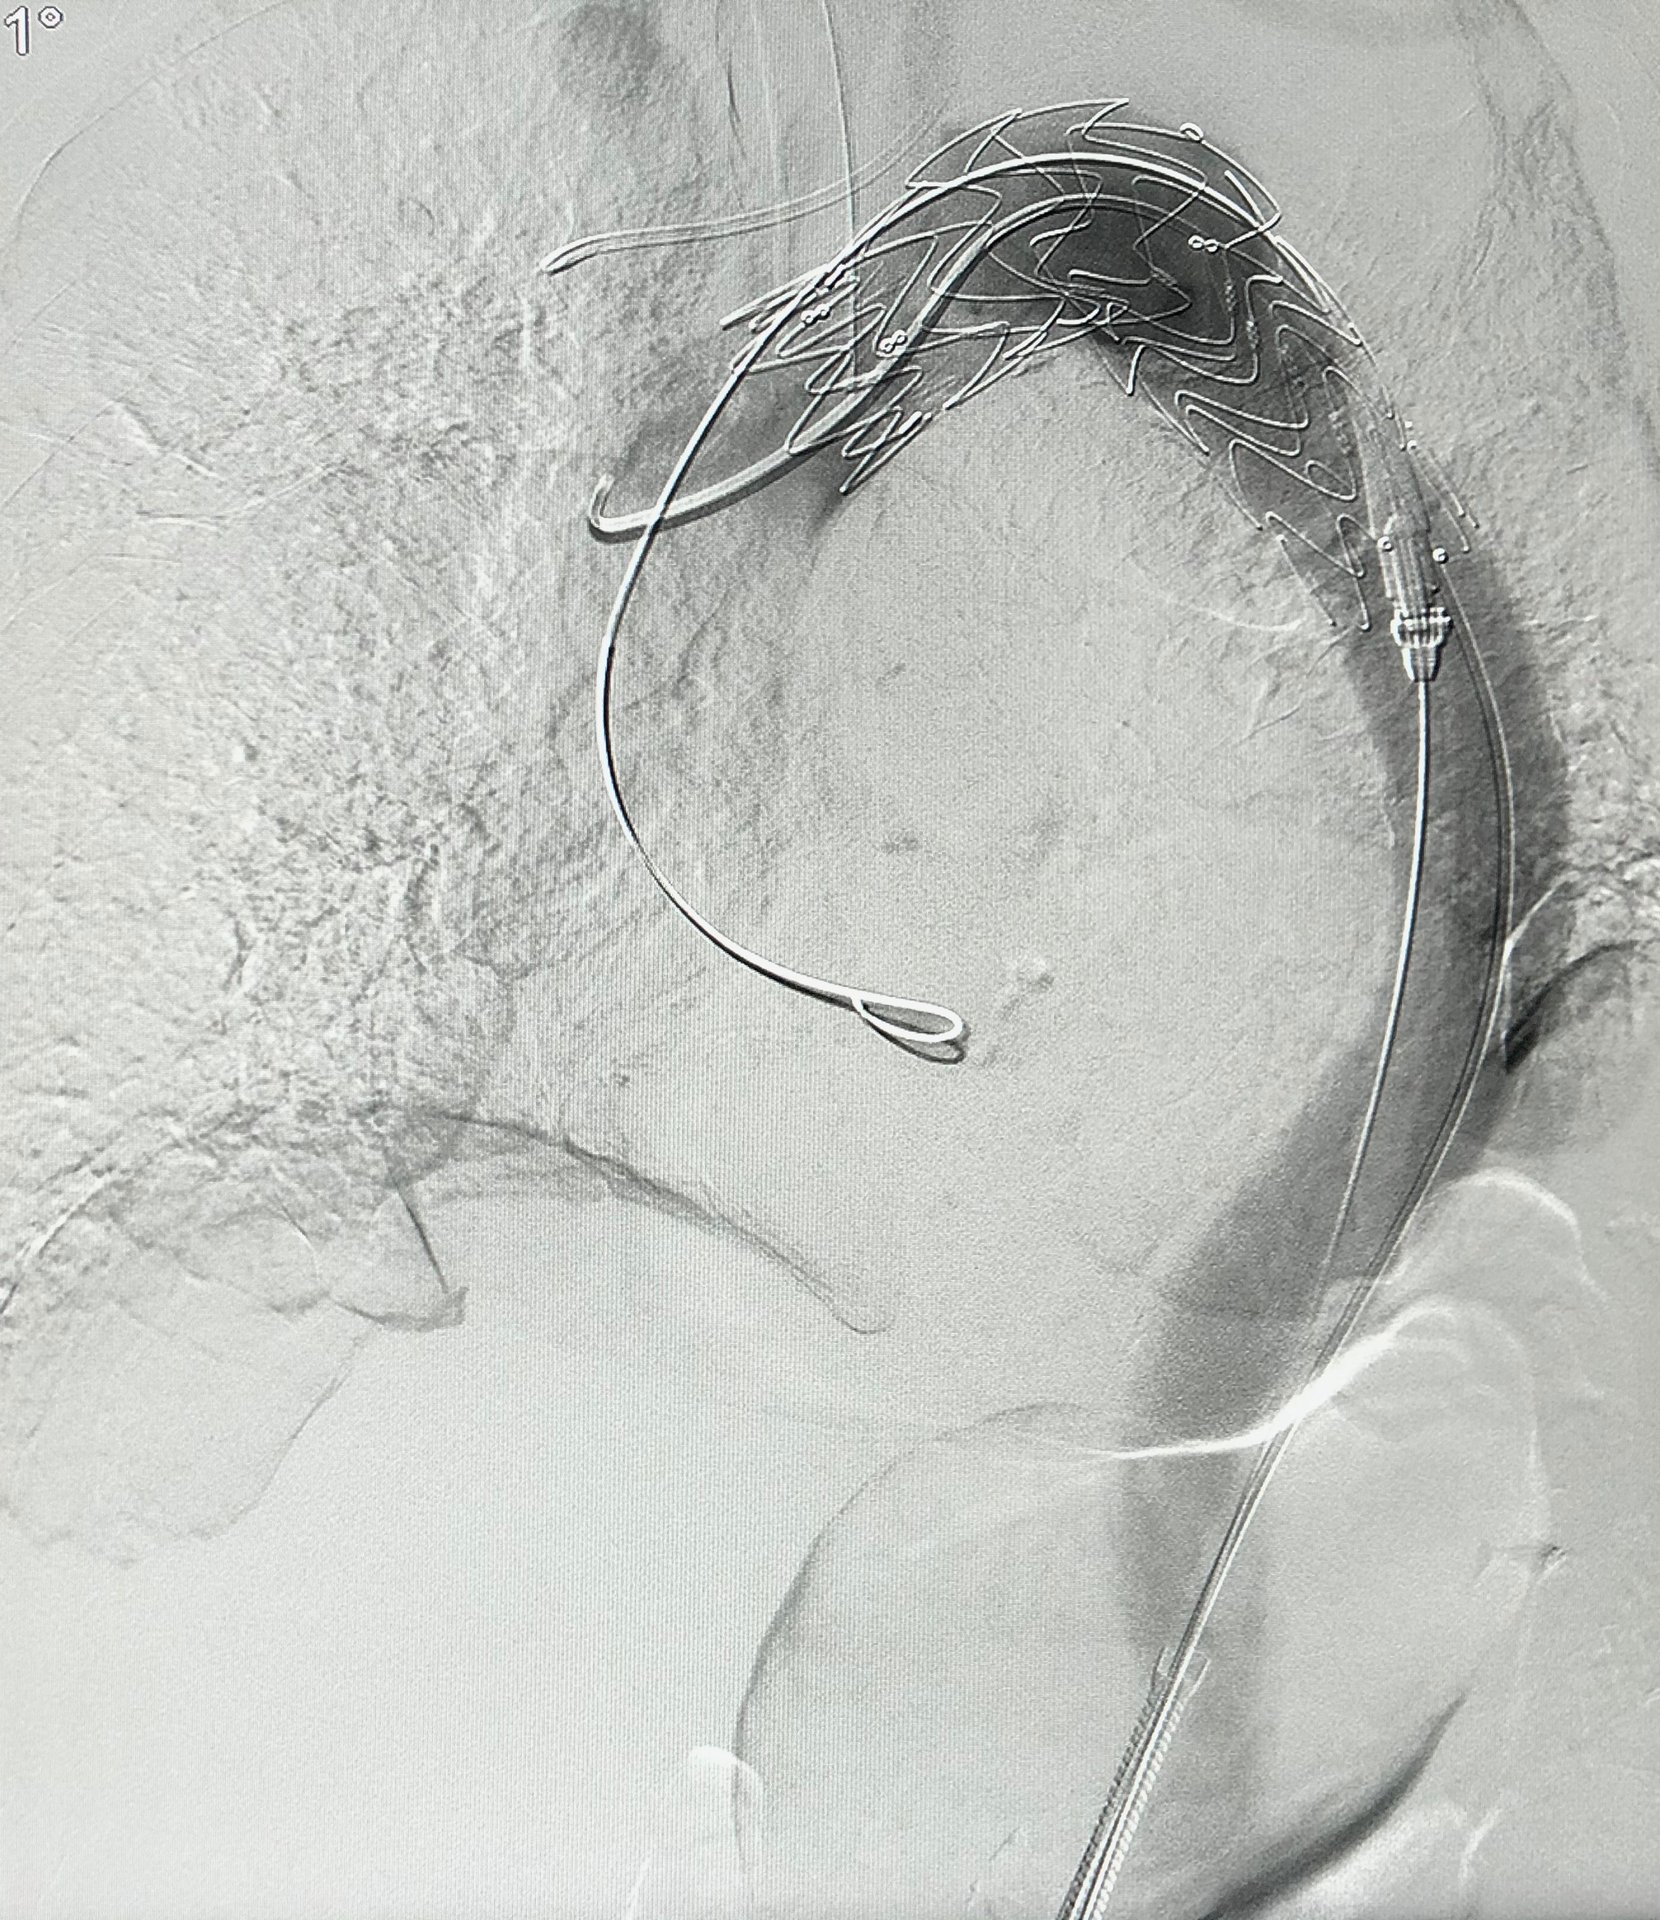

- Intrakranielle Aneurysmatherapien (z.B. Aneurysma-Coiling und Flow Diversion)

- Embolisationen von arteriovenösen Malformationen und arteriovenösen Fisteln (AVM/AVF)